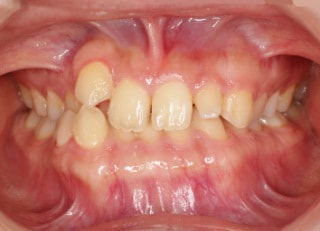

症例紹介

上顎2番矮小歯右下2番先天欠如

治療法:フルパッシブブラケット:T21

解説:下顎前突上顎劣勢長傾向で、上顎両側2番が矮小歯、右下2番先天欠如症例なので、上下前歯の幅径の比率を調節する必要があるケースです。(ご本人のご都合で治療中に来院できない期間がありました)

治療前